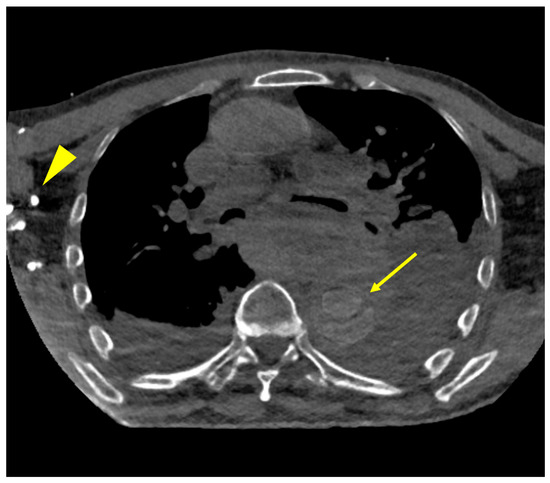

- Kaatsch, H.L.; Vollmecke, M.F.; Becker, B.V.; Dillinger, D.; Kubitscheck, L.; Wohler, A.; Schaaf, S.; Piechotka, J.; Schreyer, C.; Schwab, R.; et al. Improved Discriminability of Severe Lung Injury and Atelectasis in Thoracic Trauma at Low keV Virtual Monoenergetic Images from Photon-Counting Detector CT. Diagnostics 2024, 14, 2231. [Google Scholar] [CrossRef]